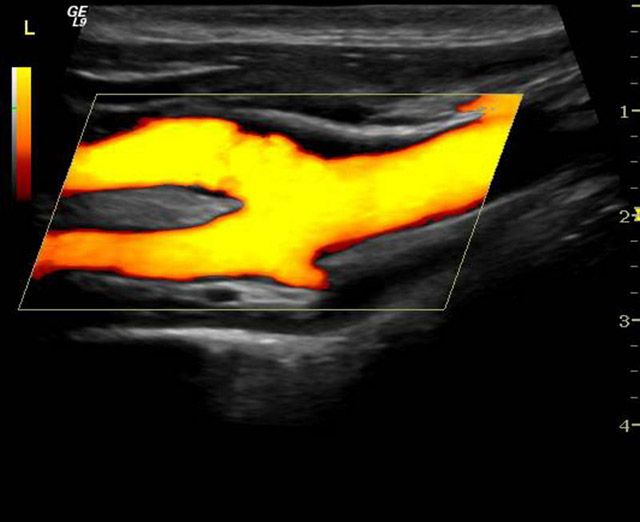

ΕΓΧΡΩΜΟ DOPPLER

Έγχρωμο doppler (triplex) αρτηριών και φλεβών

Το υπερηχογράφημα duplex έγχρωμης ροής ή αλλιώς το triplex συνδυάζει τις πληροφορίες της συμβατικής υπερηχογραφικής απεικόνισης ενός αγγείου και τις πληροφορίες εξέτασης της ροής στο αγγείο με Doppler. Επίσης, με την εξέταση αυτή ο ιατρός βλέπει πώς ρέει το αίμα στο αγγείο και μετρά την ταχύτητα ροής. Έτσι, μπορεί να ελέγξει την πορεία του αγγείου, να υπολογίσει το μέγεθός του και το βαθμό στένωσής του, αν υπάρχει.